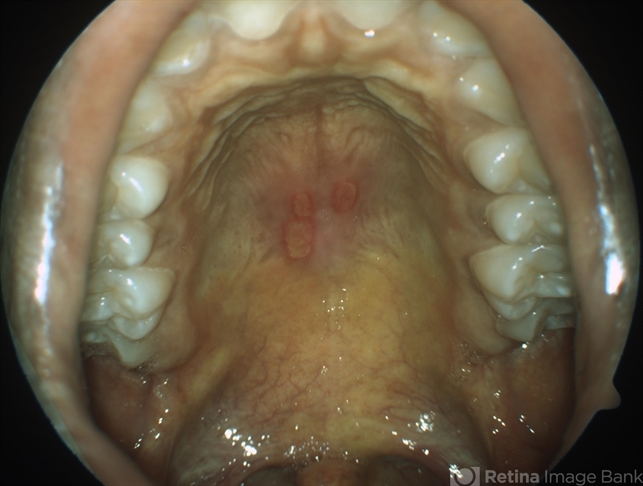

- Behcet's uveitis, vasculitis

- A 19-year-old boy presented with with recurrent oral and genital ulcers along with blurring of vision. Systemically he was HLA B-51 Positive suggesting Behcet's Disease. The photograph depicts the classic aphthous mouth ulcers seen in the Behcet's disease.